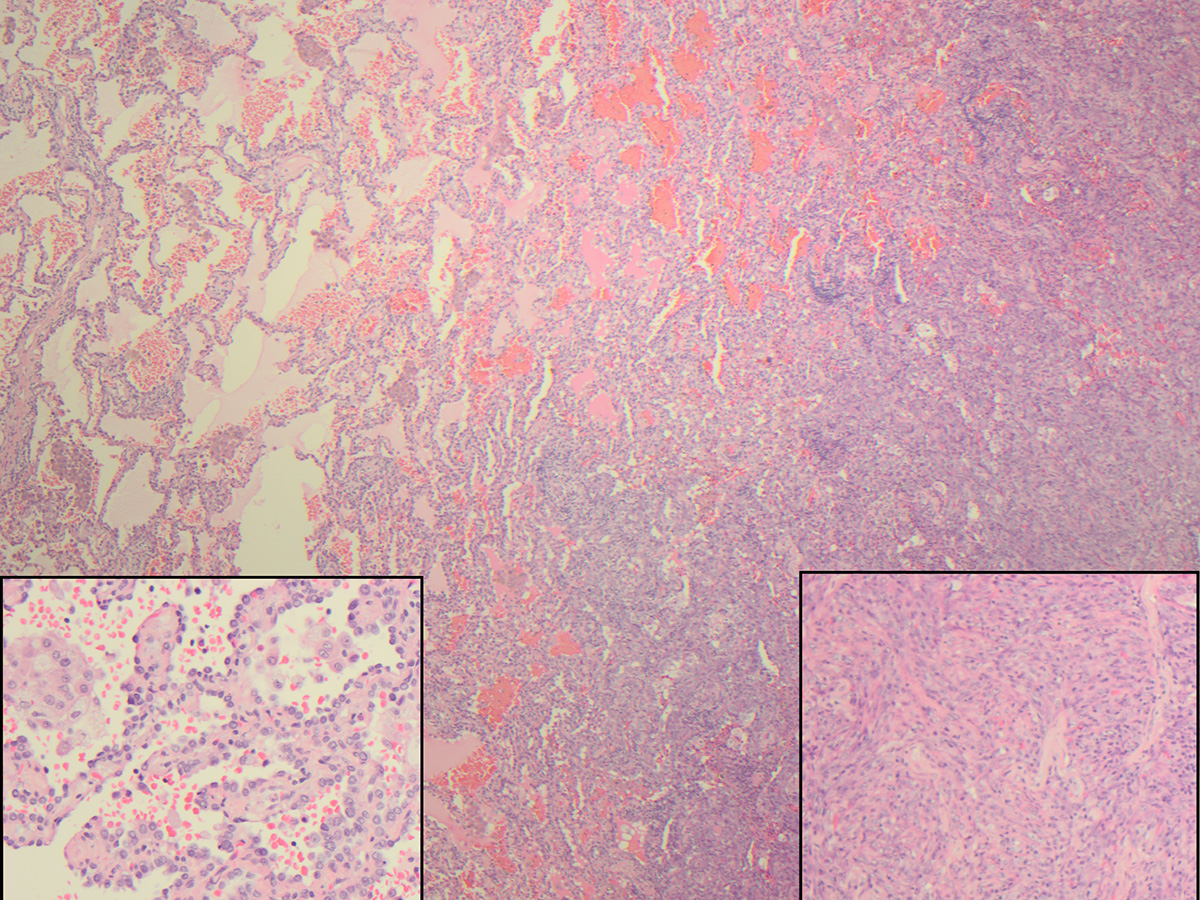

A CT-assisted lung biopsy was performed and was consistent with a diagnosis of histiocytic sarcoma, prompting a lobectomy of the right lower lobe with a wedge resection of the right middle lobe. H&E-stained slides demonstrate a biphasic tumor with sarcomatoid components and adenocarcinoma components (Figure 1). This tumor had two immunophenotypes: the adenocarcinoma component was positive for TTF-1, pan-cytokeratin, and napsin A, but negative for CD163; the sarcomatoid component was focally positive for pancytokeratin and CD163, but negative for TTF-1.